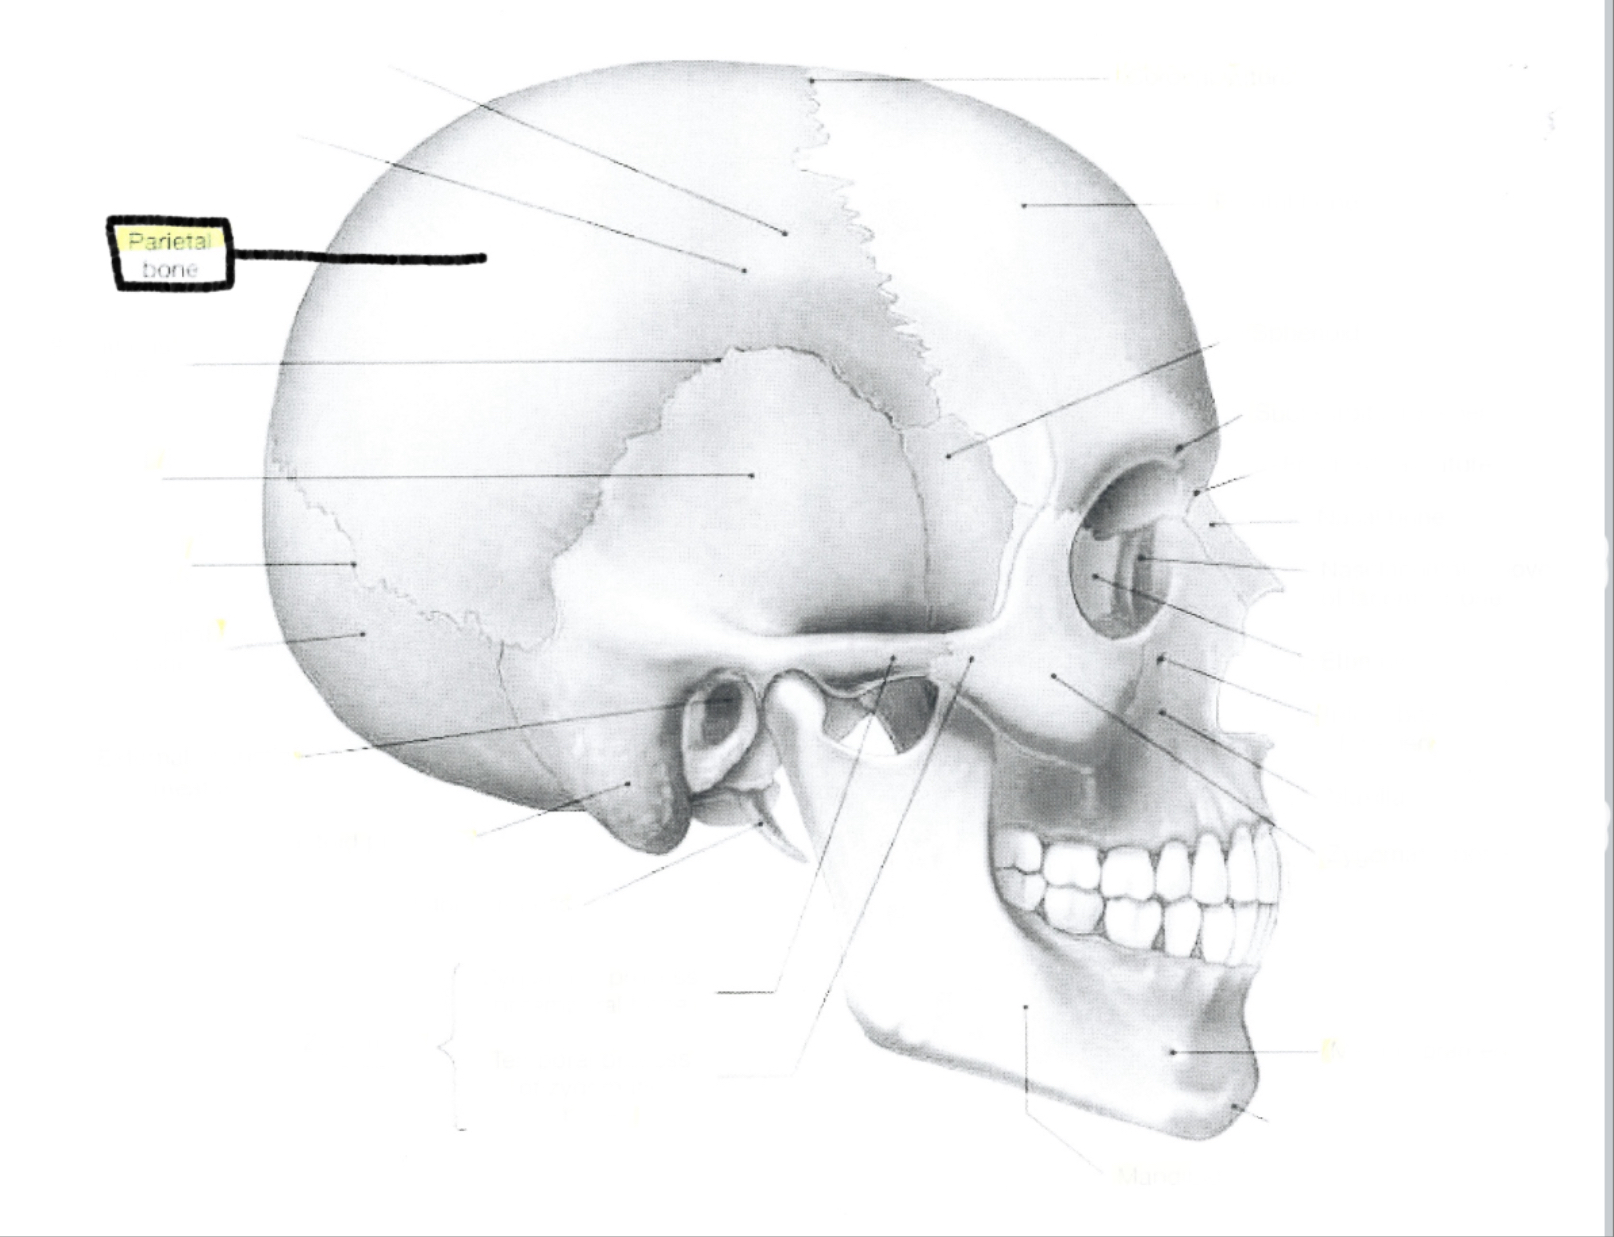

Parietal bone

Parietal bone